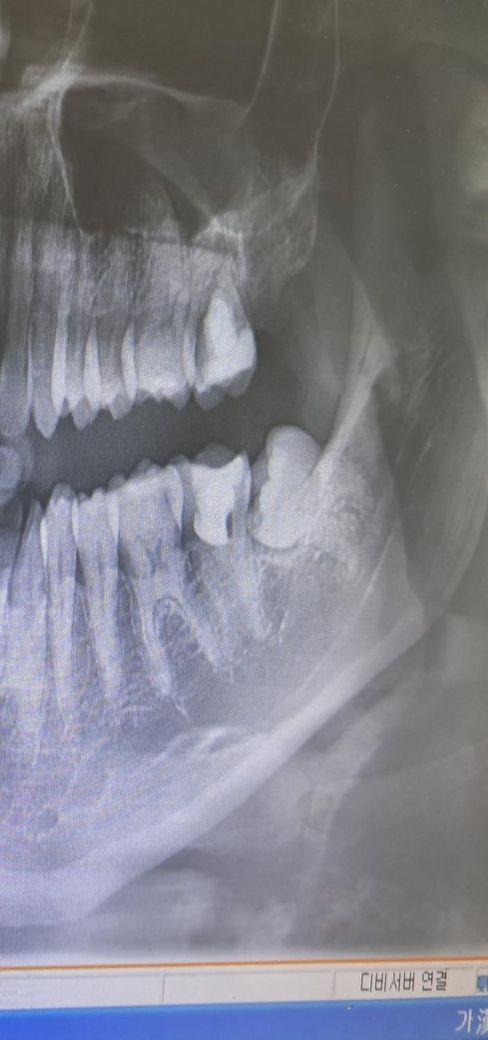

한 곳은 왼쪽 아래 어금니 신경치료했던 옆치아, 왼쪽 위 인접면충치로 인레이?로 세곳 떼워야 된다고 하셨고

• 1번 째 사진

파노라마 사진으로는 치아 사이 충치를 판단하기는 어렵고 작은 사진을 한번 찍어보시는게 좋을것같습니다. 첫번째 사진에서는 인접면 충치가 잇는것처럼 보이긴 합니다.

2. 아래 신경치료한 어금니 앞의 어금니(제1대구치)는 지금 엑스레이 사진 가지고는 단정지을 순 없지만 충치가 있을 가능성도 있습니다. 평소 사이로 음식물이 많이 끼거나 시리거나 했다면 충치일 확률이 높습니다